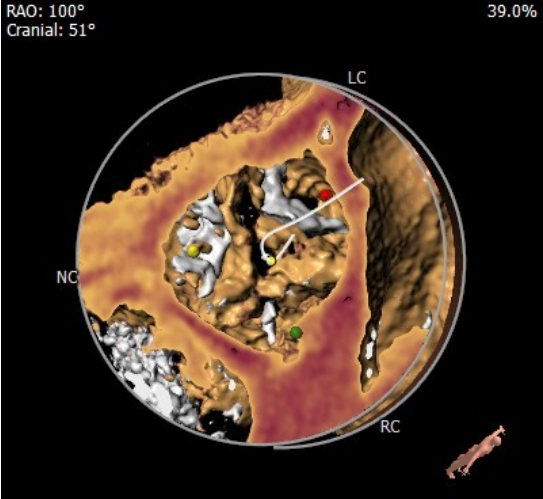

术前CT

中度钙化四叶瓣,瓣环面积:418mm²,流出道面积:476mm²,左冠开口高度:12.2mm,右冠开口高度:9.2mm。